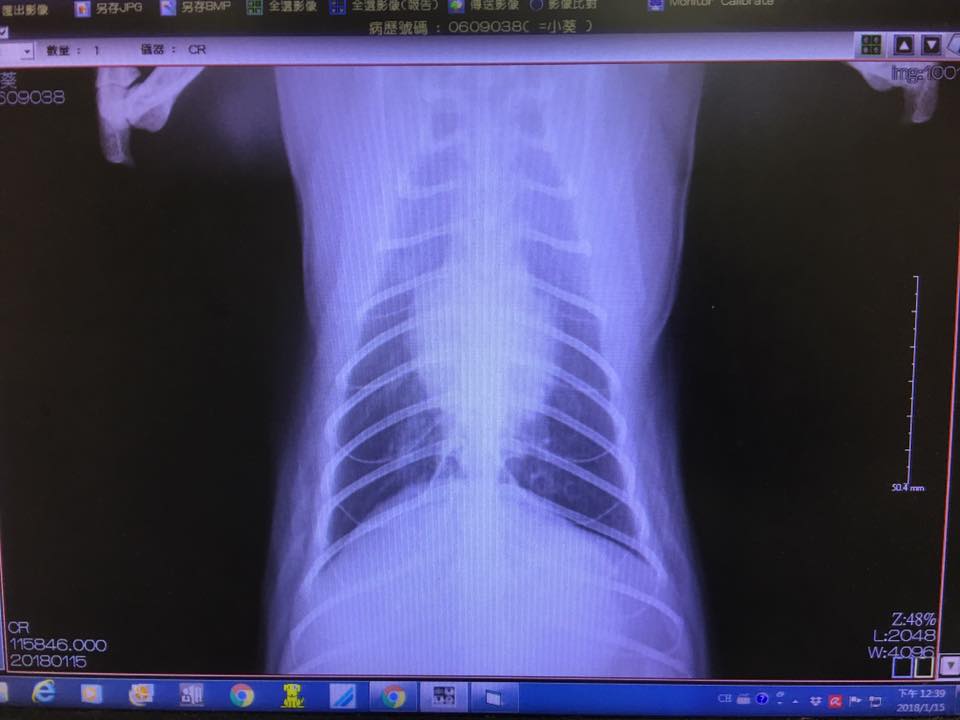

抽血檢查都沒問題,呼吸聲音大的問題已排除鼻塞問題,拍胸腔x光片檢查發現有肺部輕微發炎;口服藥有調整,有加抗生素與氣管擴張藥劑,須配合每日噴霧治療

抽血結果顯示其他都正常只有球蛋白偏高,但還在可接受範圍;拍胸腔X光看到肺臟狀況有好很多,醫師這次會把類固醇加回去但是「三天」吃一次,噴霧仍然繼續噴